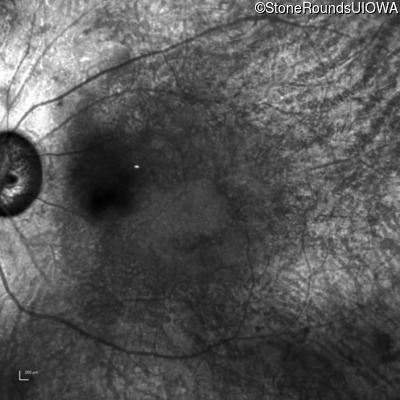

AR Retinitis Pigmentosa (IA1aiii)

Age at visit: 62 years

OD OS

This 62 year old man had poor night vision as a teenager and developed difficulty with his peripheral vision in his early forties. His parents both grew up in the small village in Taiwan.

Diagnosis & molecular findings

Disease Gene Allele 1 variant(s) Allele 2 variant(s) Inheritance mode

AR Retinitis Pigmentosa EYS Cys2139Tyr TGT>TAT Cys2139Tyr TGT>TAT AR